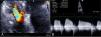

Case 2We present the case of an 80-year-old woman implanted with a permanent VDD pacemaker in 2001 for symptomatic conduction tissue disease, who underwent generator replacement due to battery depletion in February 2009. In August 2010 she went to the emergency department with a clinical setting of exertional dyspnea (NYHA class III/IV), orthopnea, edema, predominantly right quadrant abdominal pain, asthenia and anorexia, progressively worsening over the previous two months. Physical examination showed jugular vein distension, facial cyanosis, generalized edema, hepatomegaly and rapid irregular peripheral pulse; pulmonary auscultation revealed no signs of congestion, while cardiac auscultation revealed soft heart sounds and an aortic mid-systolic murmur and a low-frequency diastolic murmur at the left sternal border. The electrocardiogram showed atrial fibrillation with controlled ventricular rate alternating with ventricular pacemaker rhythm. The chest X-ray revealed cardiomegaly, obliteration of the costophrenic angles and a redundant loop of the ventricular lead at the level of the tricuspid valve apparatus, with no other significant abnormalities (Figure 3A). Laboratory tests detected slight elevation of BNP and GGT but no other relevant alterations. Echocardiography revealed thickened TV leaflets and the ventricular lead adhering to the valve and subvalvular apparatus, severely limiting opening (peak and mean gradient of 15 and 10mmHg, respectively, and estimated functional area of 0.6cm2) (Figure 4), aortic sclerosis and a moderate pericardial effusion at the left ventricular free wall (1.6cm) and large effusion at the right ventricular wall (2.4–2.1cm), with slight right ventricular diastolic collapse (Figure 3B). Right heart catheterization showed malpositioning of the pacemaker lead at the level of the TV, which was deformed, with reduced and eccentric opening (mean gradient of 11mmHg) (Figure 5). Left heart catheterization revealed a deformed and calcified aortic valve (maximum ventricular–aortic gradient of 13mmHg with preserved left ventricular function – ejection fraction 62%), and coronary atherosclerosis with wall calcification but no evidence of significant stenosis.